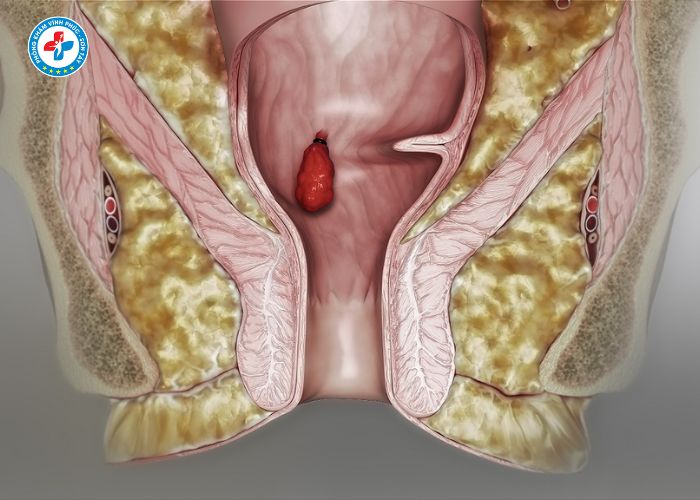

Tiêm trĩ (tiêm xơ búi trĩ) là phương pháp sử dụng thuốc chuyên dụng để tiêm trực tiếp vào búi trĩ nhằm làm xơ hóa mạch máu, giảm kích thước và làm búi trĩ teo dần.

- Chỉ phù hợp với trĩ nội độ nhẹ (độ 1, độ 2)

3. Tiêm xơ búi trĩ

- Tiêm thuốc vào chân búi trĩ

- Thuốc làm co mạch và xơ hóa búi trĩ